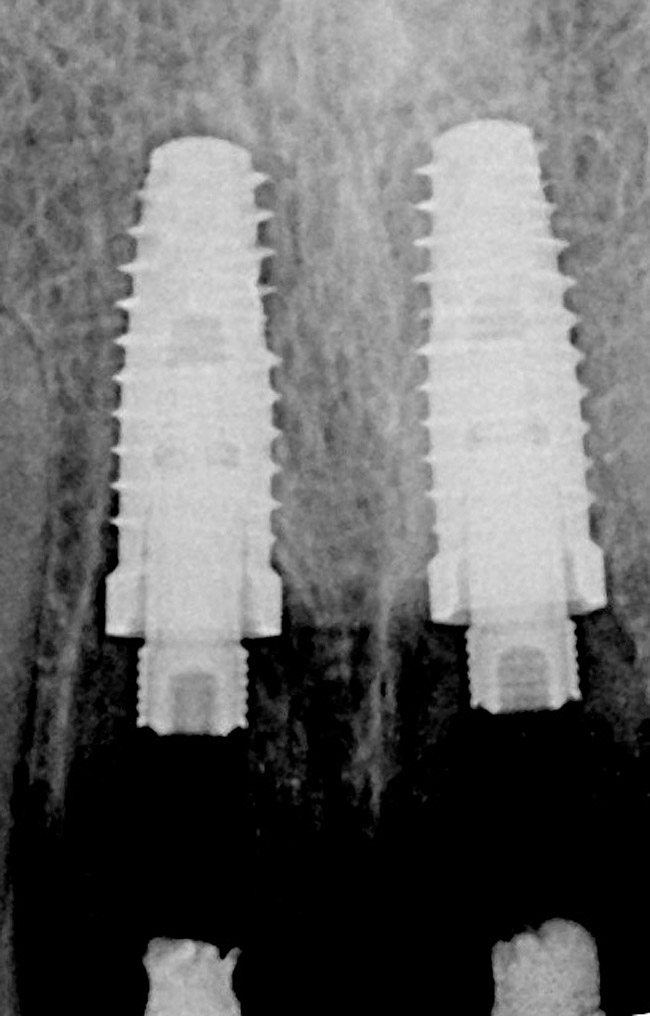

Figure 3  Periapical radiograph of implants in the Nos. 8 and 9 sites 3 years after placement. A bony peak was still present between the implants due to successful guided bone regeneration and favorable fixture spacing.

Figure 3

Figure 9   Periapical radiographs of the final implants show good bone levels and interproximal spacing between the implants and adjacent teeth.

Figure 9

Figure 10   Periapical radiograph at the time of provisionalization. Note the wide peak of bone between implants Nos. 8 and 9.

Figure 10